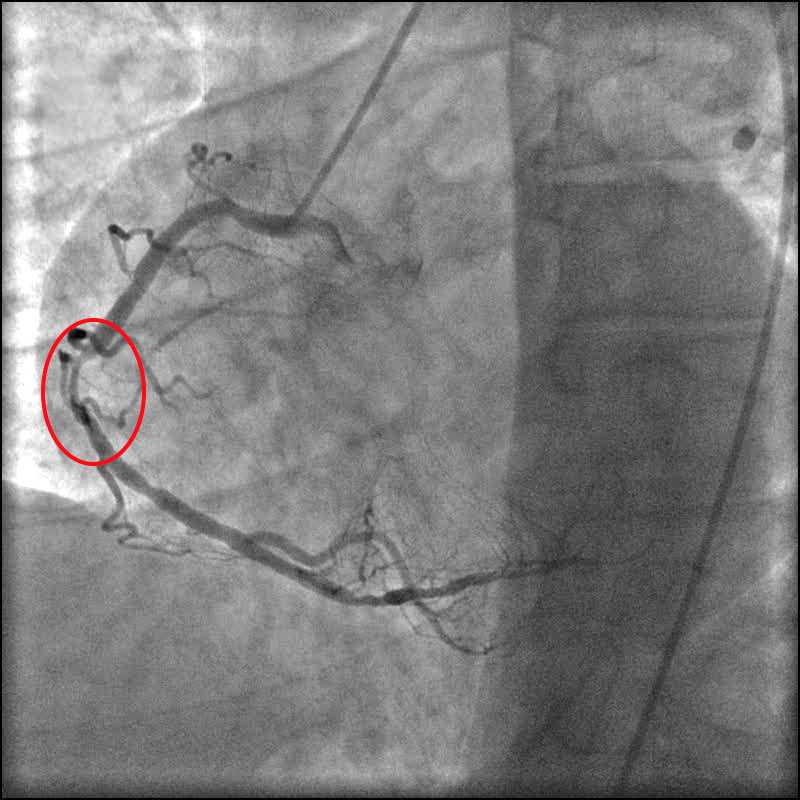

Анатомия коронарных артерий: КТ-изображения

Раздел: Снимки успеха